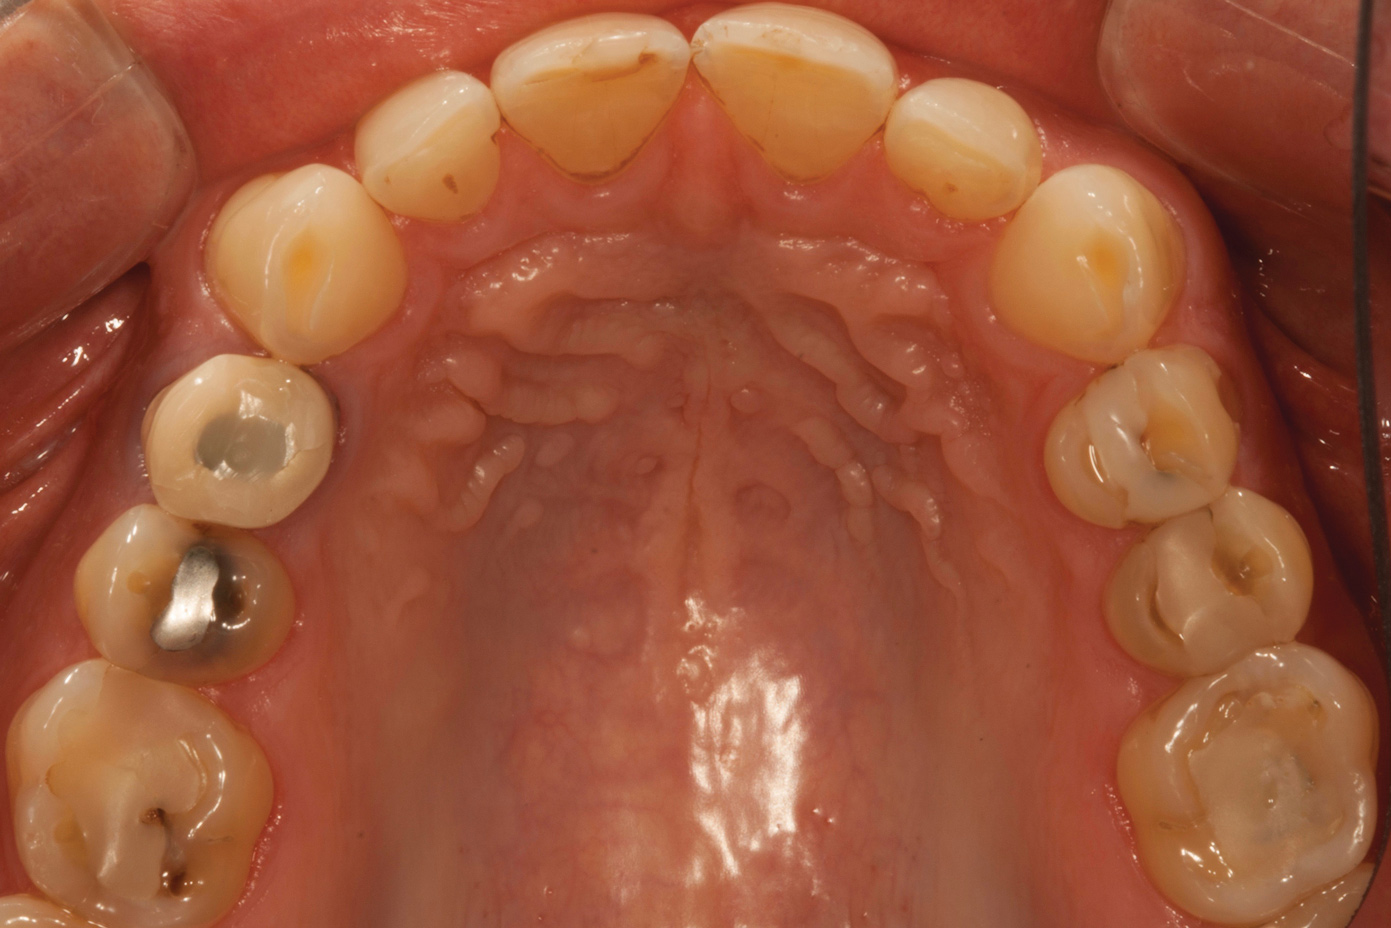

Fig 4. Preoperative occlusal view of upper arch.

Figure 4

A comprehensive examination was carried out, and preoperative photographs were taken (Figure 1 through Figure 4). The patient presented with fair oral hygiene and slight, generalized tissue inflammation. Caries and defective restorations were detected on teeth Nos. 4, 5, 13, and 14. The crown on tooth No. 12 was showing signs of leakage, and although the endodontic access cavity had been temporarily restored with composite, this endodontic re-treatment was acceptable and the tooth was otherwise symptom-free. Erosion was present on most of the posterior teeth and the cuspids, and abrasion was noted on teeth Nos. 4, 5, 10, 11, 20, 21, 22, 28, and 29. An examination of the patient's muscles, joints, and bite revealed no joint sounds, a normal range of motion, and negative joint load and immobilization tests.